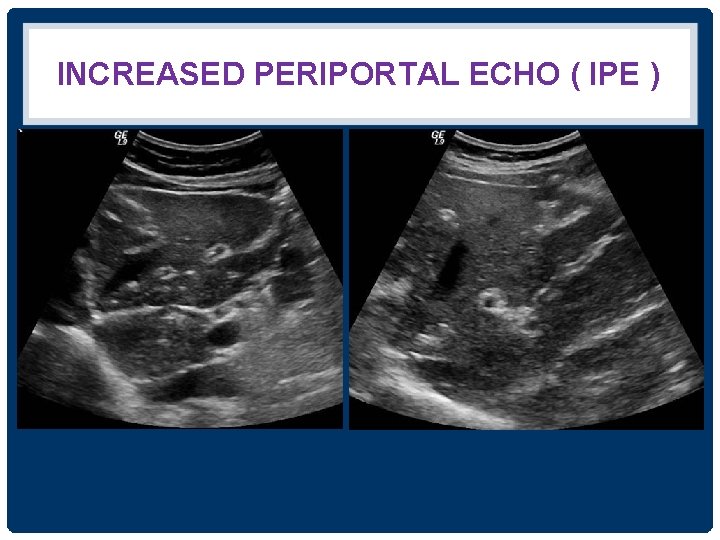

INCREASED PERIPORTAL ECHO ( IPE ) Normal echo IPE

INCREASED PERIPORTAL ECHO ( IPE )

INCREASED PERIPORTAL ECHO (IPE) GRADING = PERIDUCTAL FIBROSIS ( PDF) IPE Grade 1 is diffuse echogenic foci (‘starry sky’) minimal wall thickening of portal and segmental branches IPE Grade 2 is Ring echoes around vessels in crosssection, pipe-stems parallel with portal vein IPE Grade 3 is echogenic ruff around portal bifurcation and main stem ; main portal vein vessels wall thickening